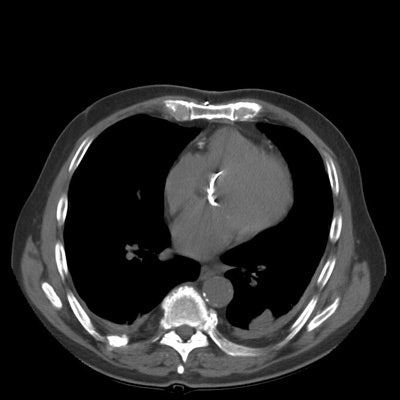

Rounded atelectasis:

The images show bilateral posterior pleural thickening. Within the left posterior lung a rounded pleural based mass-like opacity into which lung markings radiate can be identified. The left major fissure is displaced posteriorly. The lesion has remained stable for many years. The findings are consistent with rounded atelectasis. (Click small images to enlarge)